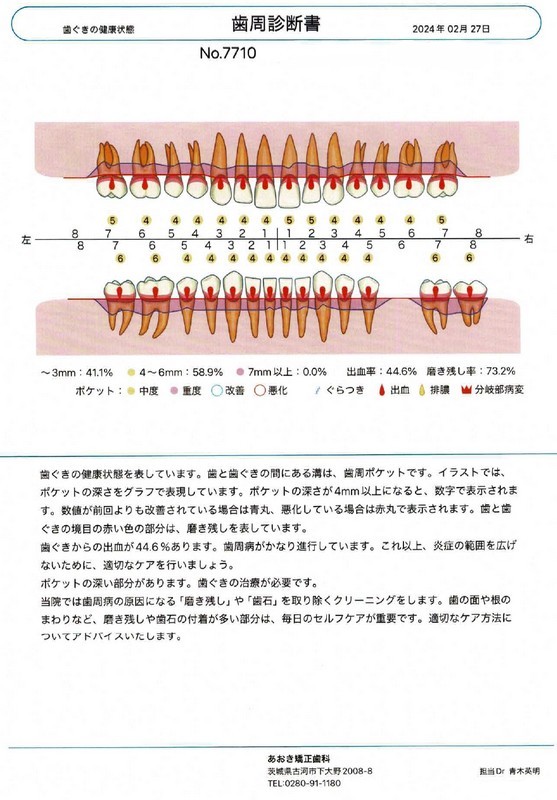

初診

初診時の主訴は「クリーニングをしたい」というご希望でしたが、歯科衛生士によるクリーニング前のチェックの際に歯肉炎の症状が認められた事と、1hのクリーニングだけでは本来目指す良好な口腔内の実現が難しいと判断しました。

歯周病治療プラン

そこで、Nさんに説明をしてカウンセリング(歯周病のPCR検査や口臭検査、マイクロスコープを使用した口腔内の細かい所までの診療)に変更させていただきました。

仕事関係での疲労やストレス、喫煙習慣、自己流の歯みがきなどもヒアリングし、口腔内のトータルでの改善を目指す為に歯周病治療3週間集中プログラム(THPアドバンス)を受ける事になりました。